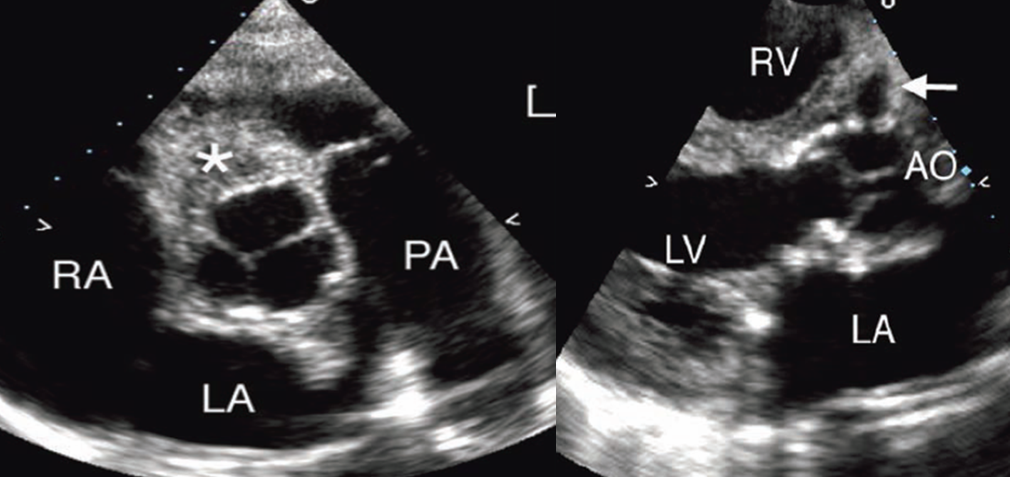

what is this?

abscess

what is shown here?

ao valve vegetation with abscess